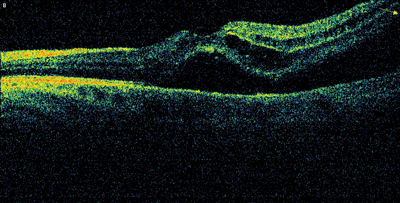

Figure 1a: OCT image of the left macula at initial presentation.

Subretinal and intraretinal fluid seen bisecting the macula and tenting of retina peripheraly in the inferotemporal direction.

Examination of the right eye showed yellow retinal lesions, thought to signify drusen. OCT scanning of the left macula demonstrated subretinal and intraretinal fluid (Figure 1a). Fundus fluorescein angiography (FFA) is not routinely performed in our unit for diagnosis of AMD, but is reserved for cases that don’t respond to treatment or present a diagnostic challenge. FFA was not done for this patient as part of her initial work-up either. The patient was referred to the one-stop macula clinic, where she was diagnosed as wet AMD and initiated on a course of three intravitreal ranibizumab (0.5mg) injections, administered four weeks apart. Visual acuity improved to 6/6. OCT showed recovery of normal foveal appearance (Figure 1b), though peripheral tenting was still present.